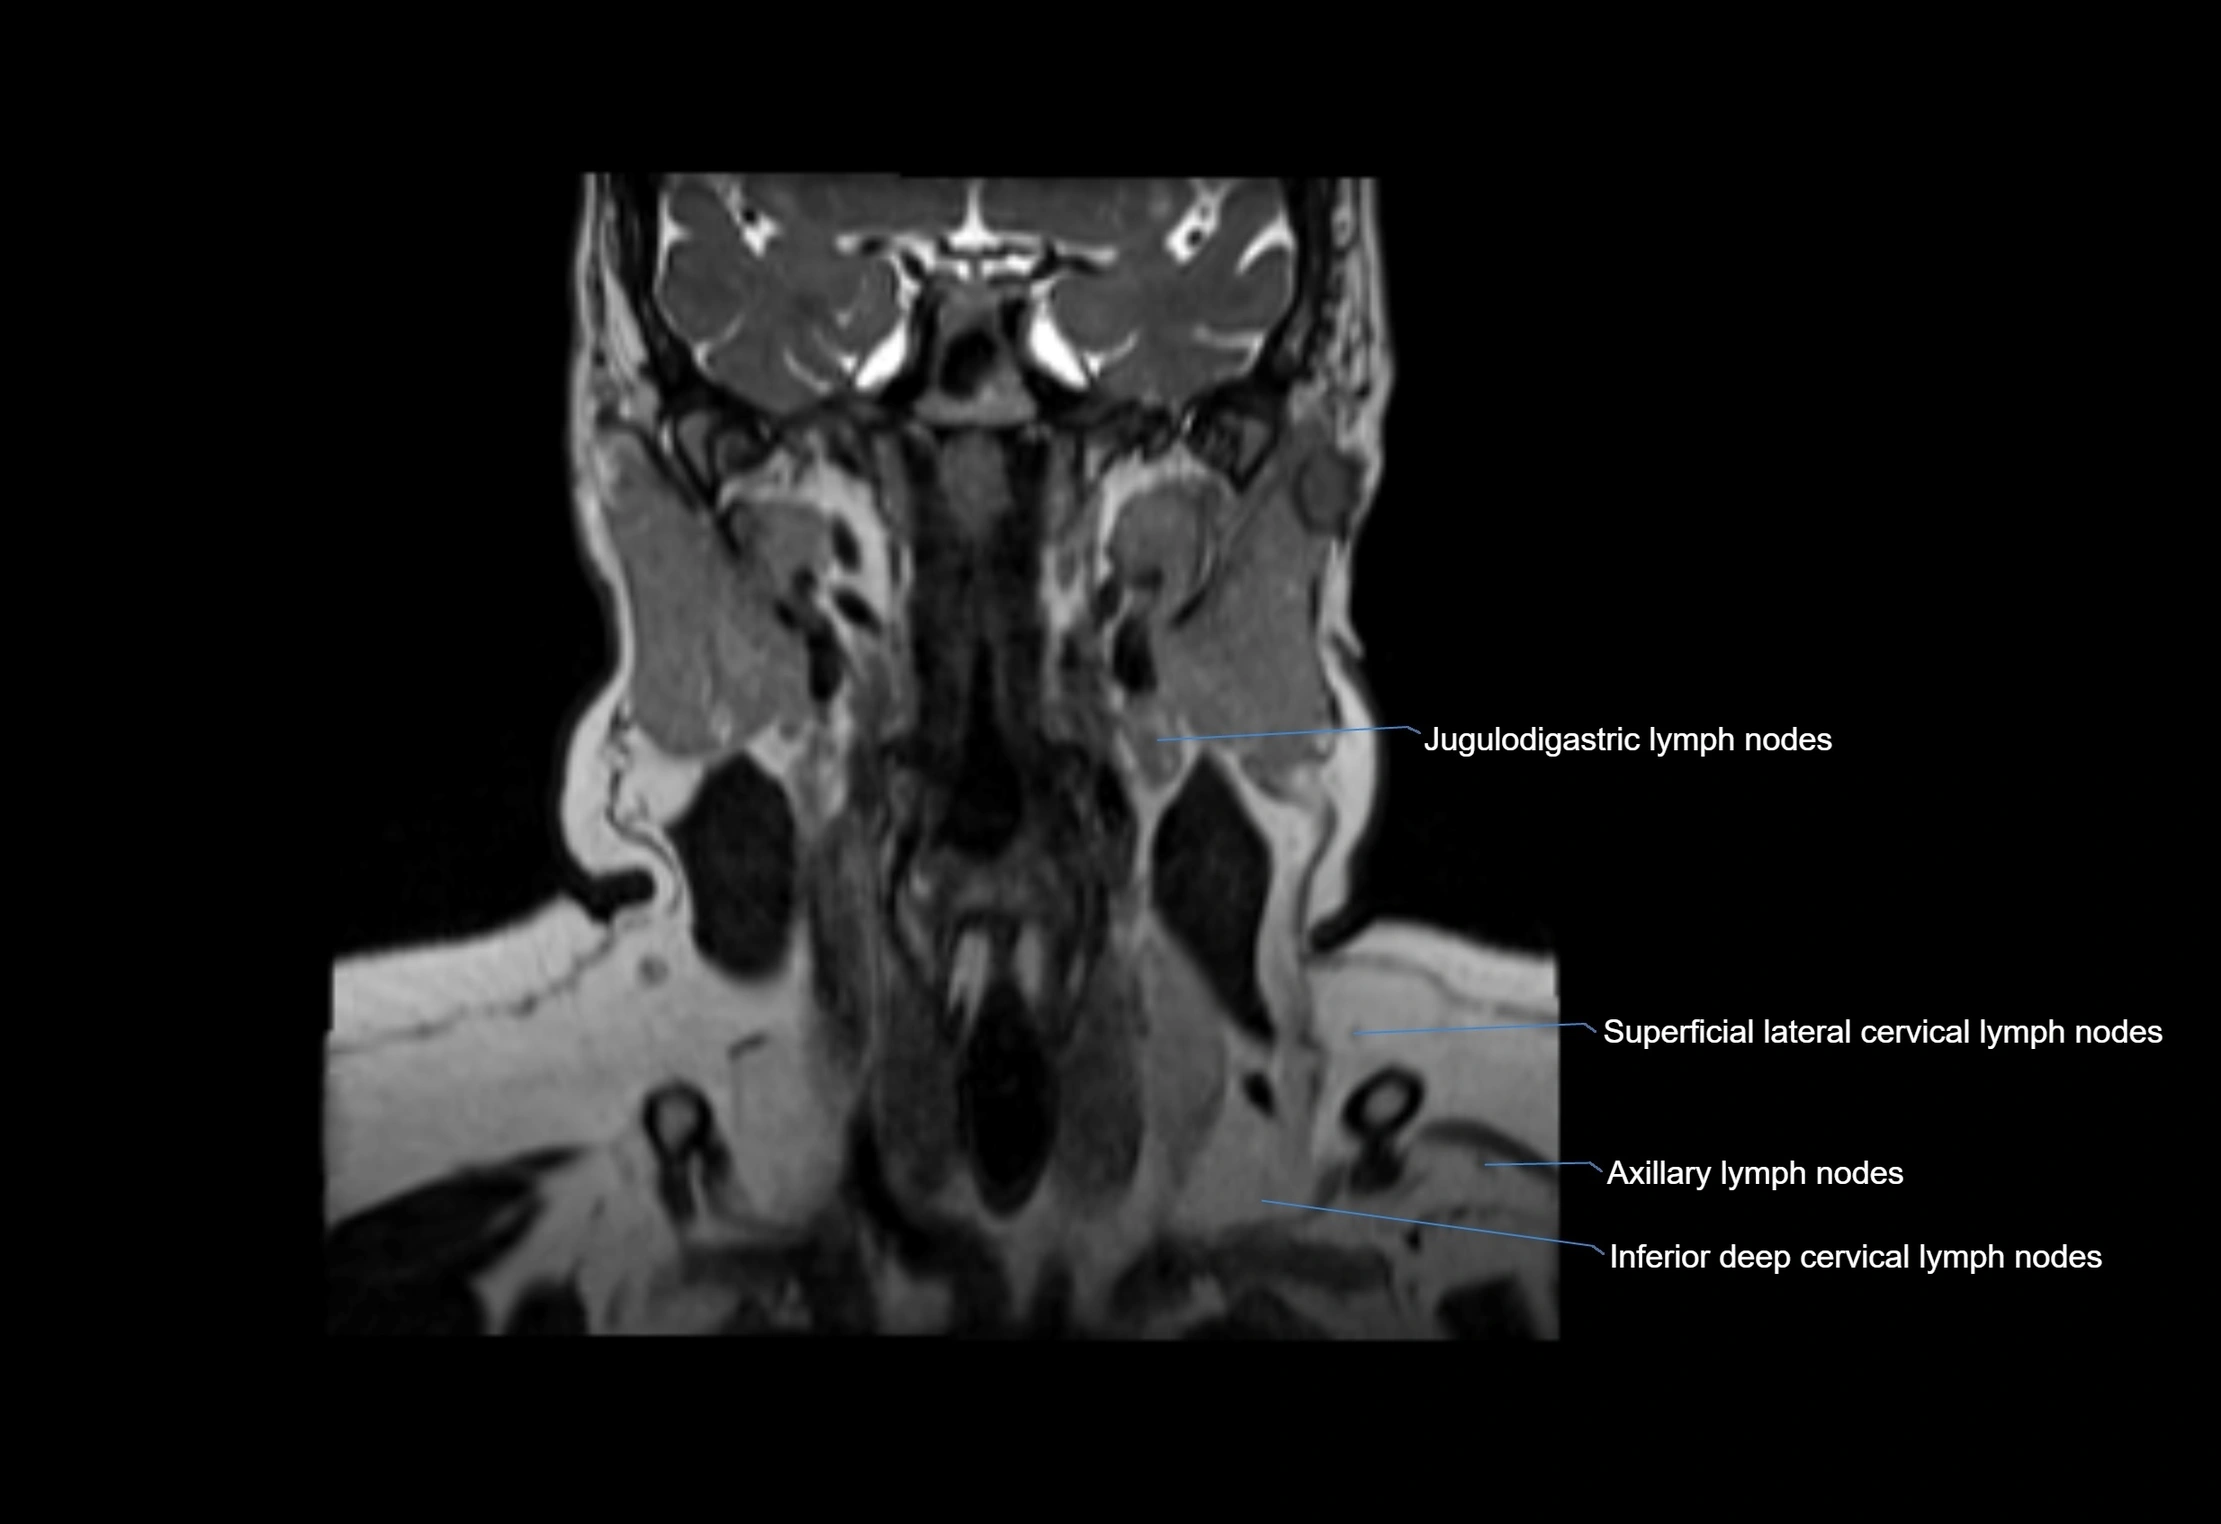

• Found along primary lymph node chains, including preauricular, submandibular, parotid, and occipital regions

• Embedded in subcutaneous fat or superficial fascia, often lateral or posterior to primary nodes

• Variable in number; may occur unilaterally or bilaterally, depending on individual anatomy

MRI Appearance

T1-weighted images:

• Normal accessory nodes appear as small, oval hypointense to intermediate signal structures within subcutaneous fat

• Surrounded by hyperintense fat, enhancing contrast for visualization

T2-weighted images:

• Nodes show intermediate signal, with surrounding fat bright

• Useful for detecting edema, inflammation, or infiltration

image